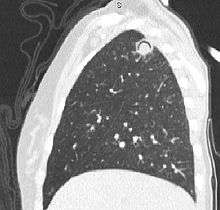

Sagittal reformat from a CT scan of the chest showing air crescent sign in a patient with invasive fungal infection. There is a rounded cavity in the apical right upper lobe, with a non-dependant soft-tissue nodule within it. Also there is some subtle ground-glass opacity surrounding the lesion.

The arrows denote an ill-defined nodular opacity in medial aspect of right upper lobe with ill-defined rim of lucency surrounding it.